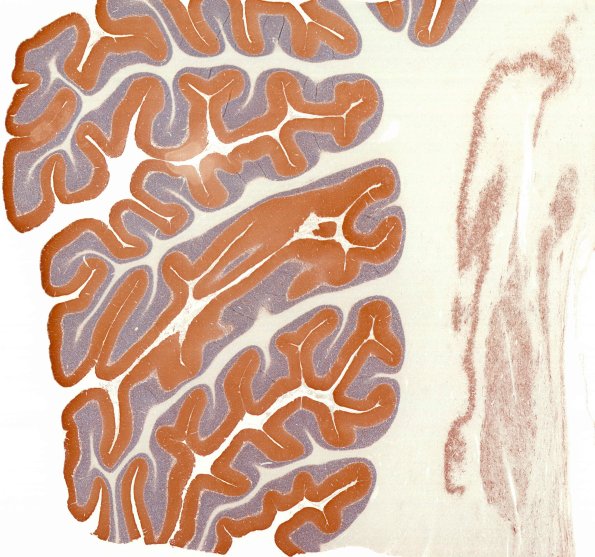

4D1 PSP (Case 4) L14 SYN whole mount

A whole mount of the cerebellum folia and deep dentate nucleus. (SYN IHC)